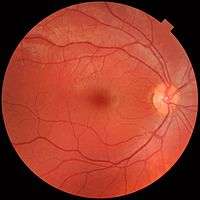

The interior of the posterior half of the left eyeball.

The interior of the posterior half of the left eyeball. A fundus photograph showing the macula as a spot to the left. The optic disc is the area on the right where blood vessels converge. The grey, more diffuse spot in the centre is a shadow artifact.

A fundus photograph showing the macula as a spot to the left. The optic disc is the area on the right where blood vessels converge. The grey, more diffuse spot in the centre is a shadow artifact.